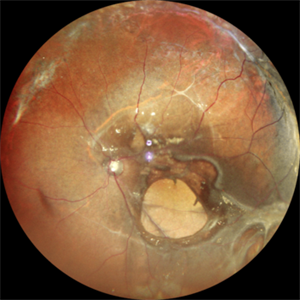

Exudative Retinal Detachment secondary to Leber's Miliary Aneurysm in a case of Retinitis Pigmentosa

Oct 13 2022 by Vaidehi Sathaye

Fundus Photograph of RE of a 23 year male patient , with an Exudative Retinal Detachment secondary to Leber's Miliary Aneurysm in a case of Retinitis Pigmentosa.

Photographer: Dr. Vaidehi Sathaye

Imaging device: Mirante

Condition/keywords: exudative detachment, Leber's miliary aneurysm, retinitis pigmentosa